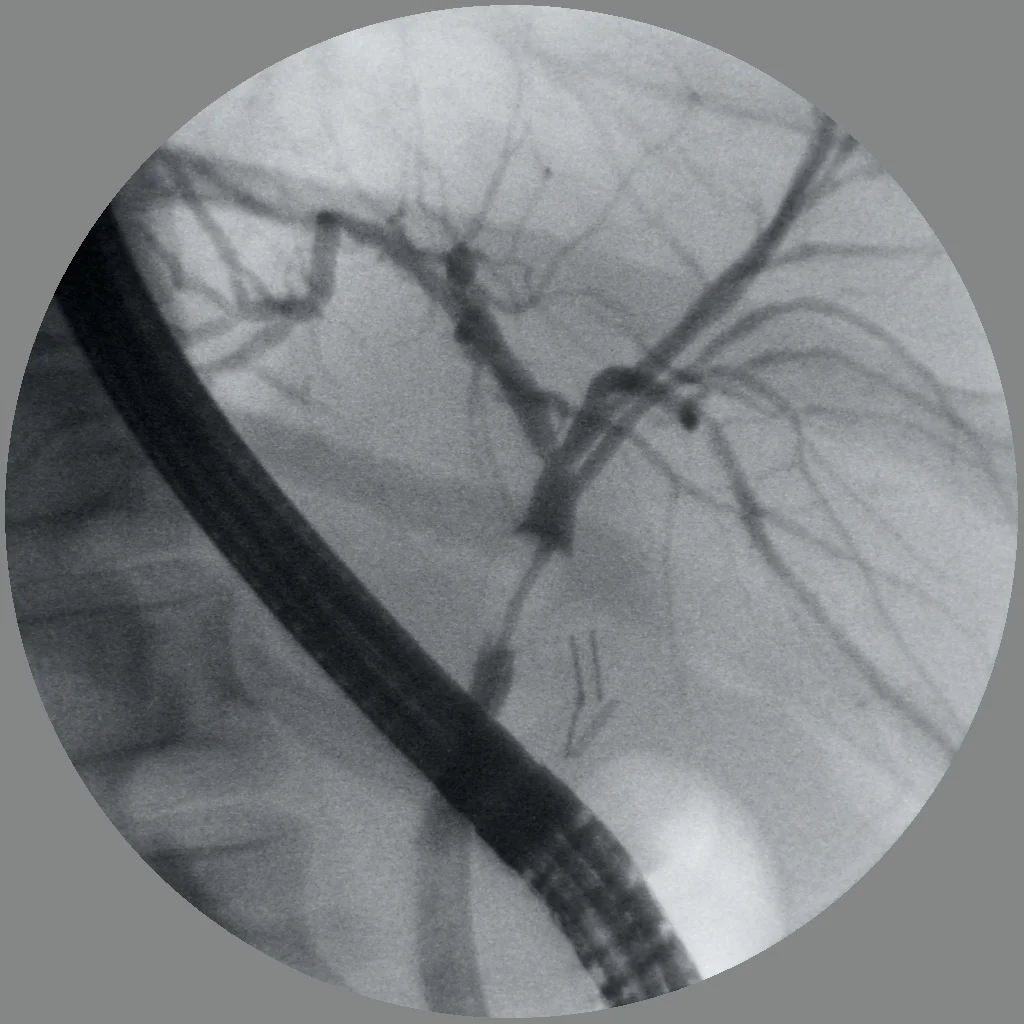

Essentially, the new Gallium scan (hereby now known commercially as NETSPOT) is the next generation of OCTREOSCAN. While it was good for its time, the gallium scan finally brings our NET community into the 21st century. The way the test works is we inject you with the drug called "68-Gallium-DOTA-OCTREOTATE". It is a form of octreotide (which binds to a receptor on many NETs called the Somatostatin Receptor) with a light bulb on the back. You let it circulate through the body, then lie in the machine where the PET scanner can take pictures of you. In general, many NETs will light up; NOT ALL WILL. However, the resolution and sensitivity is so much better than our old Octreoscan. In fact, as many of you who have seen me know, I'm holding off on many surgeries until I have it here in Denver, it means SO much to me. When I was back in Nashville, many of our patients benefited from this new technology and really had good surgical results thanks to it. That's why I feel if I can do a better surgery for you, then I want the best information possible. I have a couple of YOUTUBE videos on the technology. Take a look and then you'll see what I see.